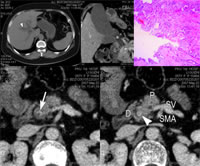

患者女,56岁,上腹不适半月,巩膜皮肤黄染伴皮肤搔痒10天。

图1 CT平扫,示肝内胆管增宽(箭头)

图2 CT增强扫描,沿胆总管纵轴曲面多平面重组(curved MPR),近横轴位平面,示胆总管扩张(星号),胰腺内段下段壁增厚,增强,管腔闭塞(箭号)

图3 手术病理:壶腹部中-高分化导管腺癌,浸润壶腹壁全层与相邻纤维脂肪组织、胰腺实质及十二指肠肌层(HE染色,×100)

图4 CT增强扫描门静脉期,胆总管下端水平,左、右两图像相差2 mm。可见胆总管壁弧形增厚,增强明显(箭号),直至完全闭塞(箭头)。图中P-胰头,SV-脾静脉,D-十二指肠,SMA-肠系膜上动脉, 百拇医药